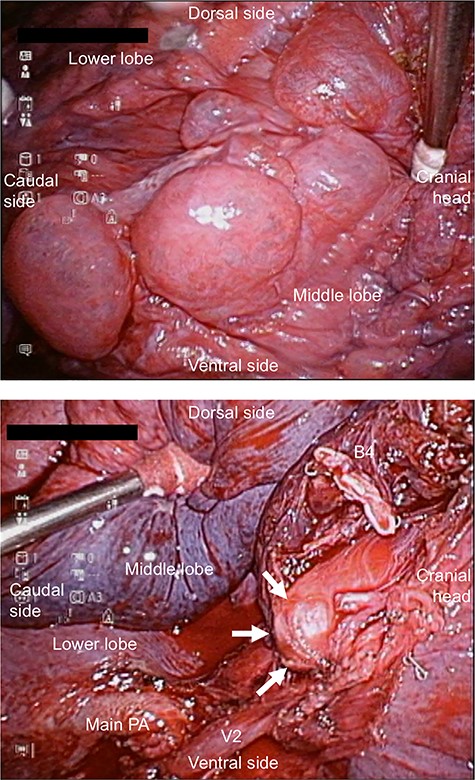

The patient underwent thoracoscopic right middle lobectomy and S3 partial resection using four ports. Intraoperatively, emphysematous changes on the right middle lobe and a part of the upper lobe were observed (Fig. 2a). Moreover, although the area between the middle and lower lobes was well lobulated, the area between the upper and middle lobes was incompletely lobulated. There were no abnormalities of the pulmonary arteries or veins. The blind-end of B5 was identified (Fig. 2b). Right middle lobectomy and S3 partial resection were performed by thoracoscopic surgery. Pathologically, B5 was not connected to the bronchial tree (Fig. 3), and a dilated mucus-filled bronchus was observed. There were fibrotic and emphysematous changes in the proximal and distal side of the mucinous impaction, respectively. These findings were consistent with the pathologic diagnosis of B5 bronchial atresia. He was discharged with good lung expansion.

(a) Intraoperative view showing extensive emphysematous changes. (b) Intraoperative view showing the blind-end of B5. B, bronchus; PA, pulmonary artery.